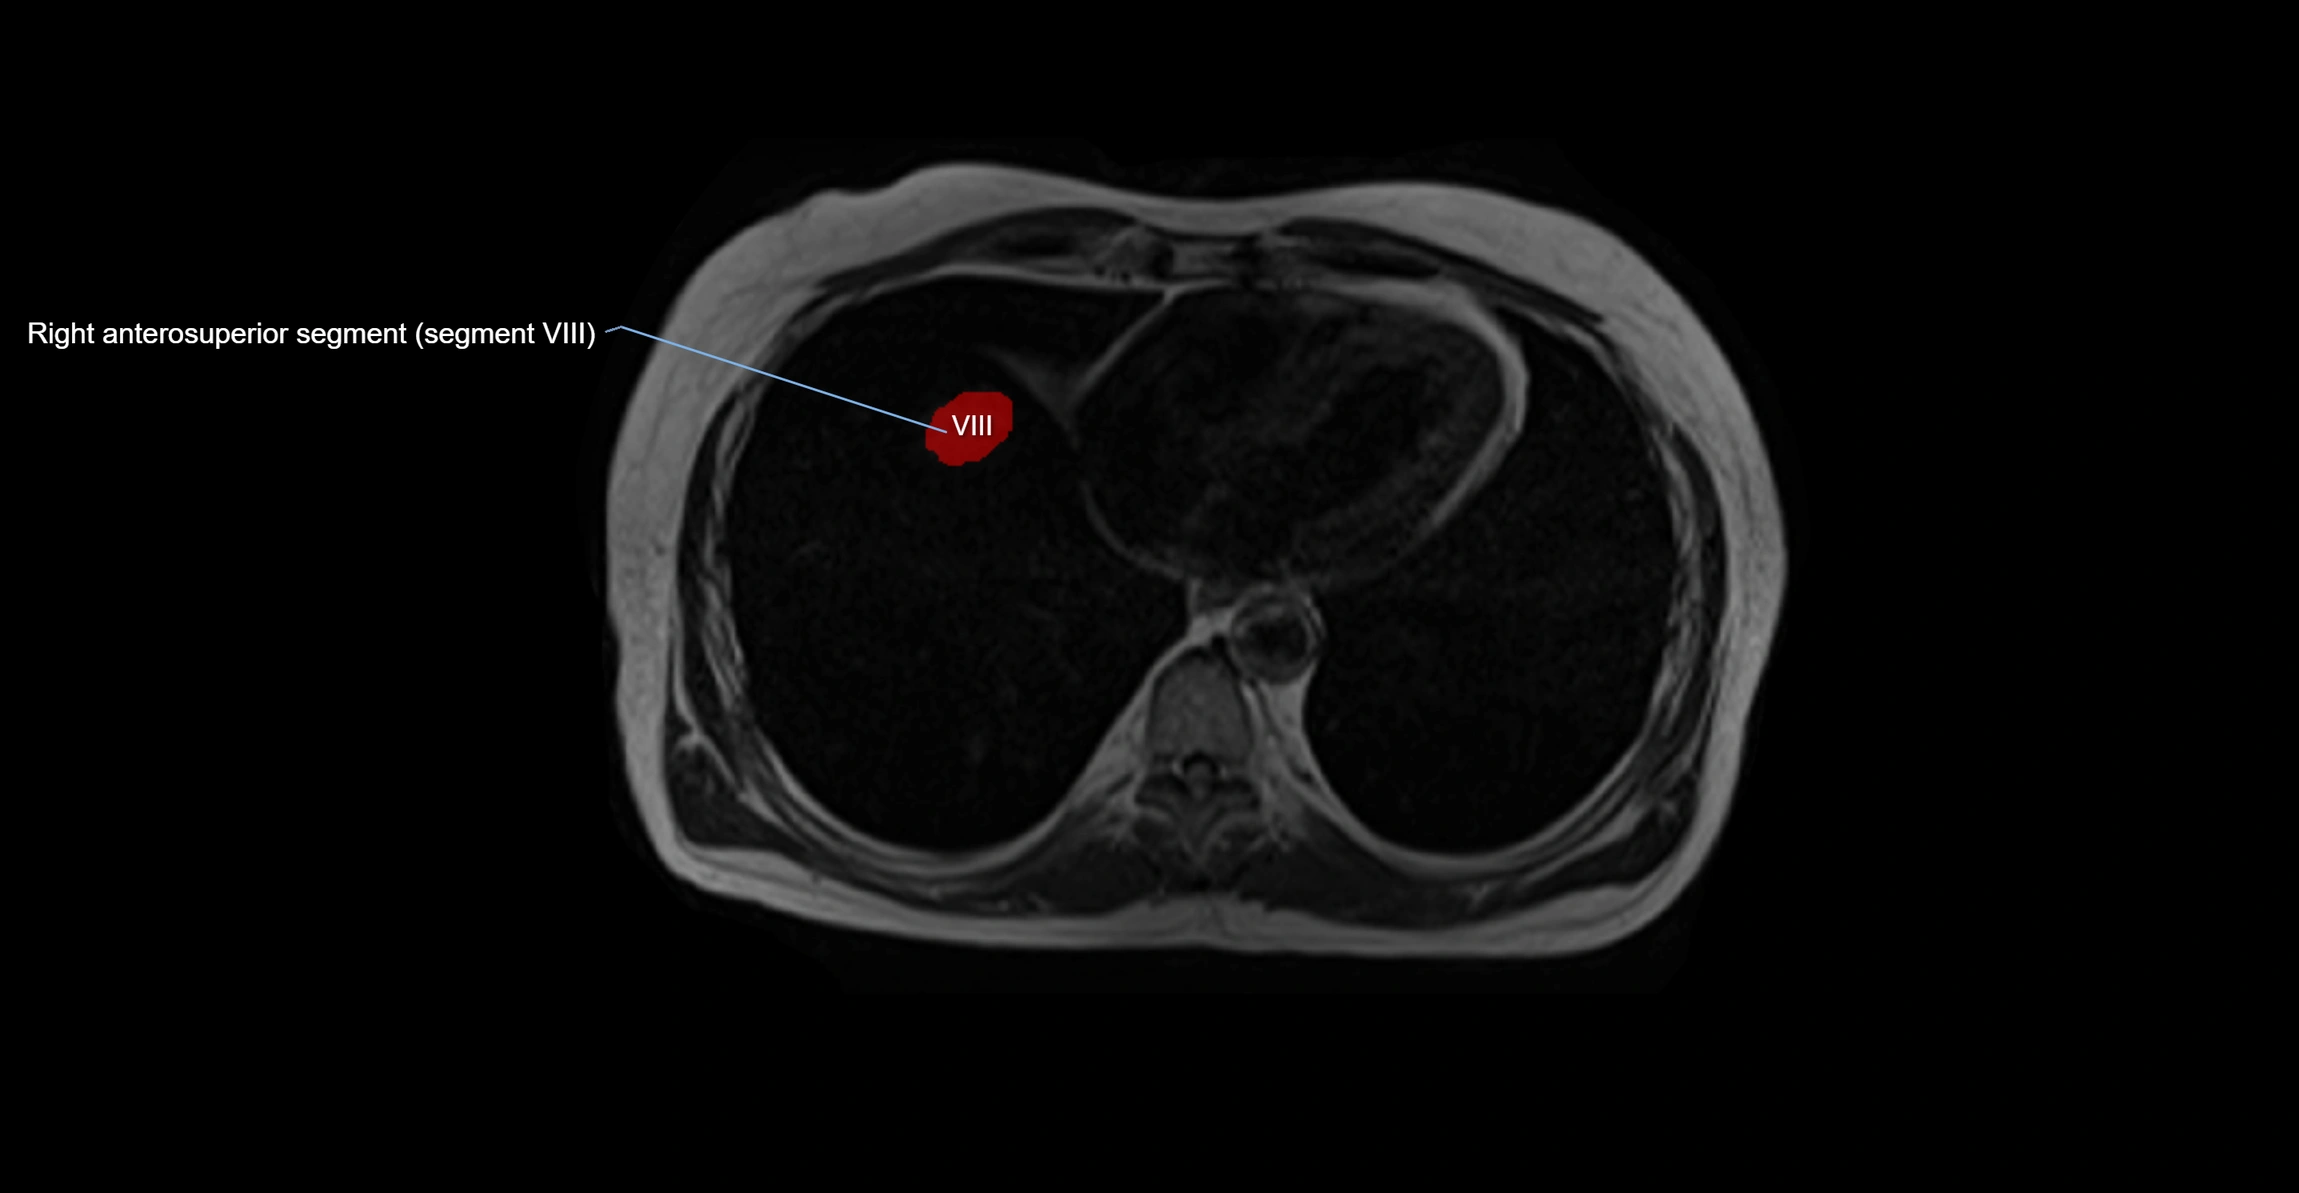

The caudate lobe of the liver is a distinct anatomical subdivision of the liver, designated as segment I in Couinaud’s classification. It lies on the posterior surface of the liver, between the fissure for the ligamentum venosum (left boundary) and the groove for the inferior vena cava (IVC) (right boundary). Superiorly, it is related to the posterior liver surface, and inferiorly it is separated from the left lobe by the porta hepatis.